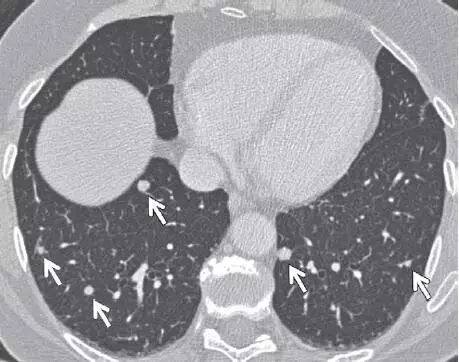

8. 转移性结节

图 8 CT 图像,显示继发于转移性甲状腺癌,以下肺分布为主的多个不同大小实性结节(箭头)。